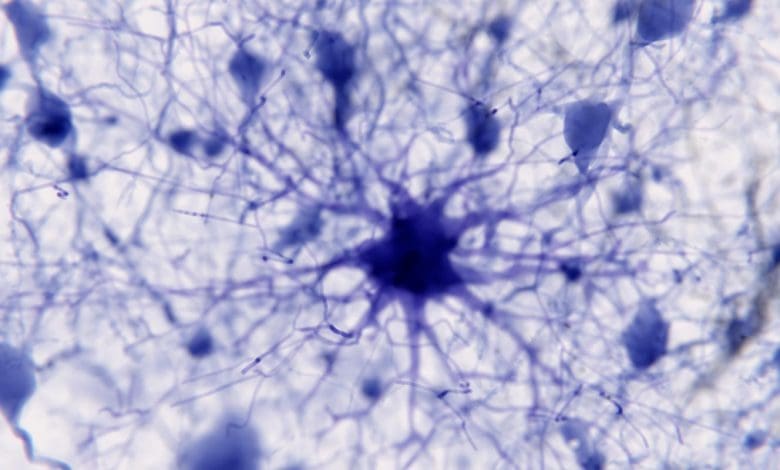

Baru dalam beberapa dekade terakhir neuroglia, sekelompok sel beragam yang ditemukan di otak yang melakukan berbagai fungsi untuk mendukung neuron, menjadi subjek penelitian. Sebelumnya, penelitian otak sangat berfokus pada peran neuron.

Sel lainnya, neuroglia, diyakini berfungsi sebagai staf kebersihan otak, menjaga lingkungan tetap sesuai untuk sinyal saraf yang optimal. Kemudian, para ilmuwan menemukan bahwa neuroglia memiliki sistem sinyalnya sendiri yang berbeda dari sinyal listrik yang dikeluarkan neuron. Sel glia memiliki sinyal kalsium.

Bagian dari neuroglia, yang disebut astrosit, tampaknya terkait erat dengan cara kerja sinapsis di neuron, dan karena sel-sel ini berperan dalam respons stres otak, ada kemungkinan bahwa sel-sel tersebut terkait dengan beberapa kondisi kesehatan mental.

“Sinyal kalsium adalah pendorong utama bidang ini karena kami menemukan bahwa mereka memiliki mekanisme rumit untuk memberi sinyal satu sama lain, ke neuron, dan ke pembuluh darah di otak,” kata Vijayaraghavan. “Kami sebelumnya mengira mereka adalah sel yang tidak dapat dirangsang, namun sebenarnya ini adalah bentuk rangsangan yang unik.”